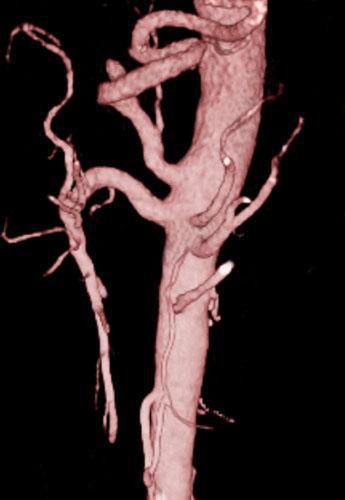

Arteria renal torácica